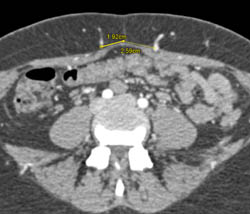

DIEP Flap Planning